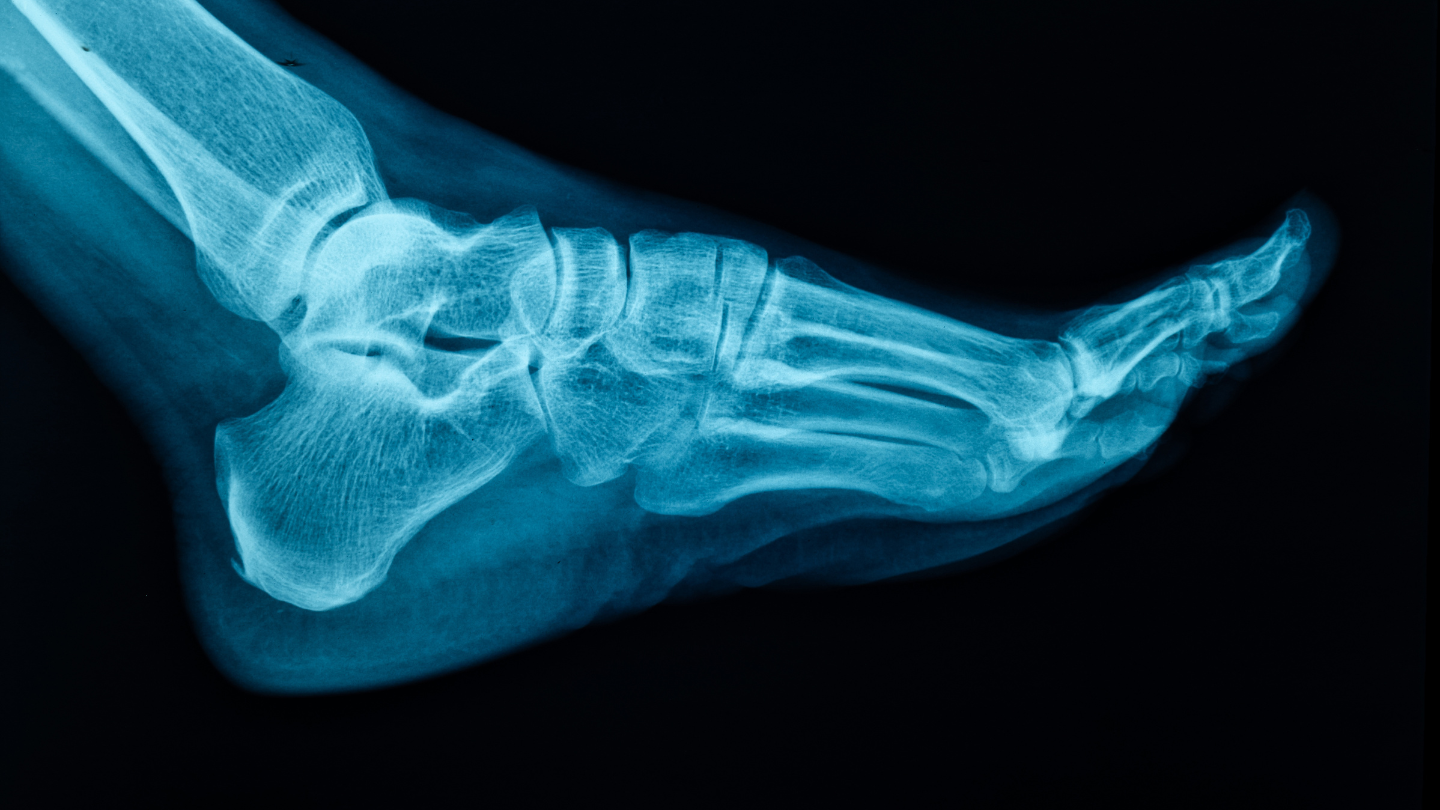

Trước tiên, bác sĩ sẽ thăm khám lâm sàng: Kiểm tra dấu hiệu sưng, bầm, biến dạng và khả năng chịu lực của chân. Tuy nhiên, chỉ dựa vào lâm sàng chưa đủ để xác định loại gãy. Chụp X-quang là phương pháp cơ bản và quan trọng nhất:

- Giúp phân biệt gãy nội khớp hay ngoài khớp.

- Đánh giá góc Bohler - một chỉ số quan trọng trên phim nghiêng (góc này bình thường từ 25 - 40 độ; nếu giảm dưới 20 độ thường gợi ý gãy xương gót chân với mặt khớp bị sập).

Khi X-quang chưa rõ ràng hoặc nghi ngờ gãy phức tạp, chụp CT-scanner sẽ được chỉ định:

- Cung cấp hình ảnh 3D chi tiết, đánh giá mức độ di lệch, số mảnh gãy và tổn thương phần mềm.

- Là cơ sở quan trọng để lựa chọn phương pháp điều trị phù hợp, đồng thời giúp tiên lượng hồi phục.

Chẩn đoán hình ảnh chính xác đóng vai trò then chốt trong việc giảm nguy cơ biến chứng và cải thiện kết quả phục hồi lâu dài.